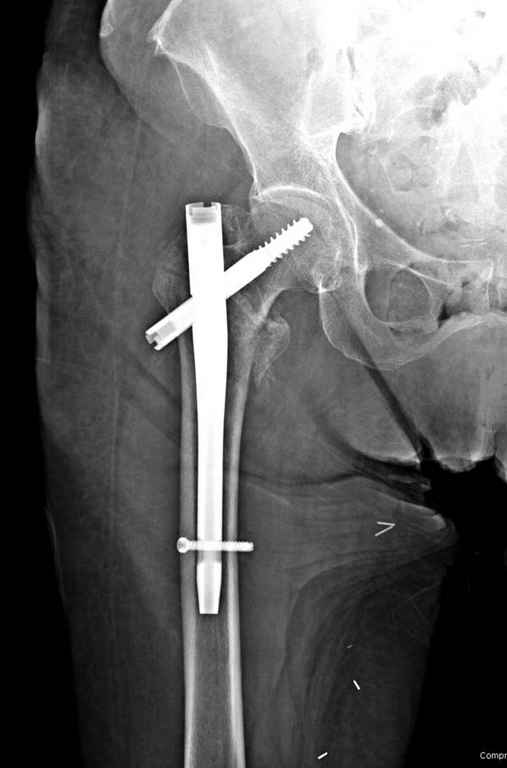

Вашему вниманию представляется похожий случай, пациентке 70, осложнился в течение одного месяца после операции. Ревизия с заменой сустава, кабельная фиксация на трохантер. При установке в дистальном диафизе обнаружен тонкий кортикальный слой и сделана профилактика от возможного перелома аллографтом.

С приходом менее агрессивных блокируемых цефаломедуллярных гвоздей (Gamma 3 и другие) изменилась тактика лечения. Несмотря на то, что вся стабильность держится вокруг одного блокирующего винта, в большинстве случаев гвозди приводили к успеху.

Из накостных, хороший результат дают проксимальные пластины от Synthes или Smith&Nephew, но из-за риска осложнения доступов многие предпочитают гвозди.

В данном случае в головке бедра и в вертлужной впадине огромный дефект, навряд ли удалением импланта или заменой на другой можно сохранить сустав.